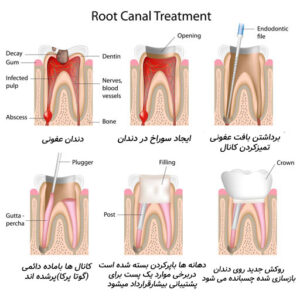

روت کانال (Root Canal Therapy) چیست؟

گاهی اصطلاح «روت کانال» به درمانی اشاره دارد که در آن پالپ عفونی از درون کانال خارج و فضای داخلی ریشه تمیز و پر میشود.

در اینجا دوباره اهمیت تفاوت کانال و ریشه دندان مشخص میشود: کانال، بخش داخلی ساختاری است؛ اما روت کانال، فرایند درمان آن بخش محسوب میشود.

مراحل درمان روت کانال

بیحسی موضعی و ایزولهکردن دندان

باز کردن دسترسی به کانال

تمیز کردن و شکلدهی با فایل اندودنتیکس

پرکردن کانال با گوتاپرکا و سیلر

بازسازی تاج دندان با روکش